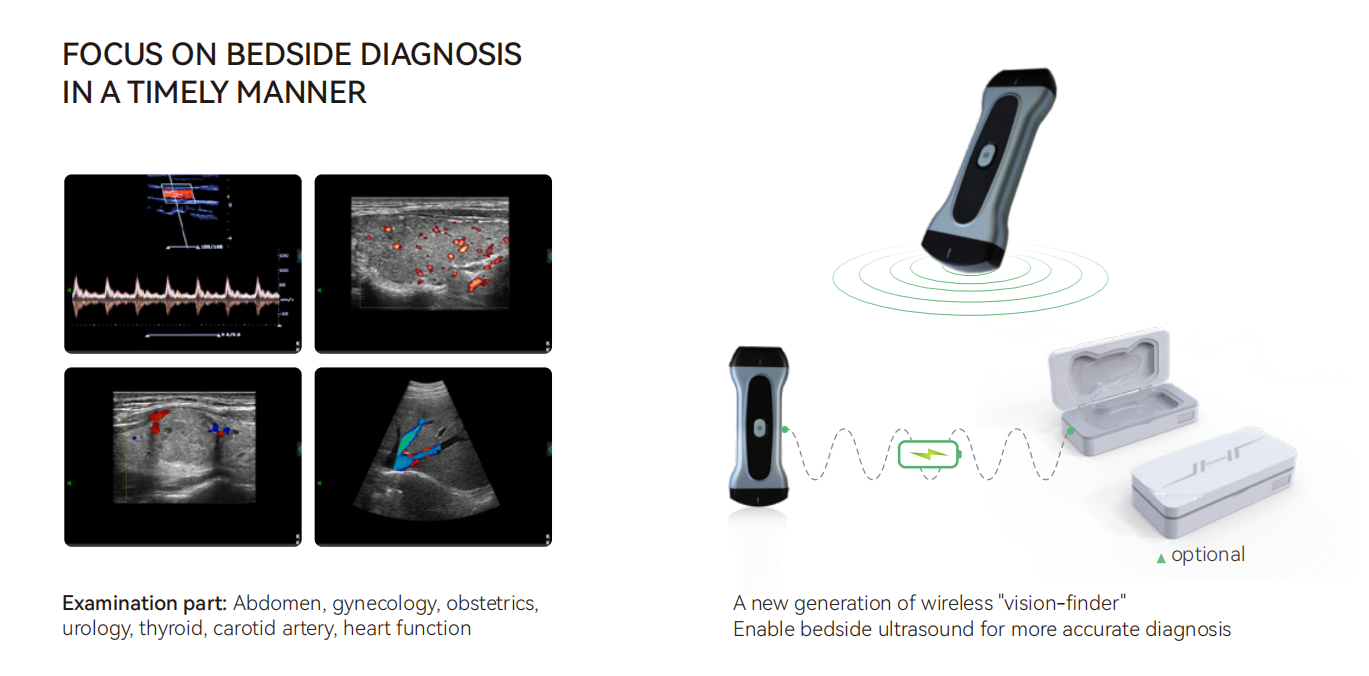

Can be connected with every terminal of iOS Android and Windows system

Battery:Removable big capacity lithium battery

Display Mode:B, M, CF, PW, PDI, DPDI, Needle Enhancement

Measure Function:OB,distance,area of a circle,Velocity,blood flow measure,fetal heart,heart rate